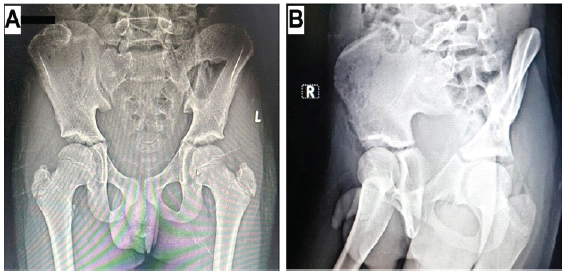

Dissection along the iliac crest was not performed to prevent physeal damage. Hemostasis was achieved by covering the bleeding bone end with bone wax. Adequacy of resection was confirmed under fluoroscopy. The abdominal wall musculature, and subsequently the surgical wound, was closed in layers. Histopathologic examination confirmed the pre-operative diagnosis of osteochondroma and showed the presence of hyaline cartilage with a fibrous perichondrial covering over osseous tissue (Fig. 2). The post-operative period was uneventful. There was no tumor recurrence at 6 months postoperatively (Fig. 3).

Figure 3: Post-operative radiographs of the first patient at the most recent follow-up. (a) Anteroposterior view of the pelvis and (b) iliac oblique view of the pelvis (Potential patient identifiers have been blacked out).